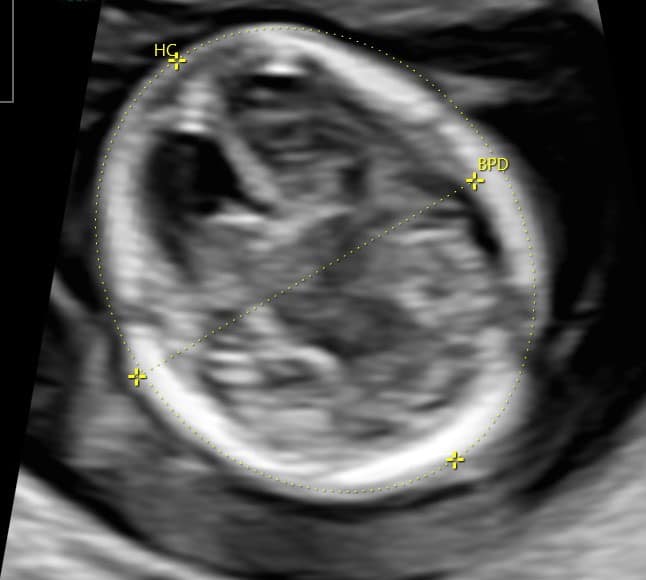

Magzati koponya, arc: koponyacsontok, agykamrák a bennük látható érfonatokkal, a hátsó koponyagödör fejlődő területei, agytörzs.

Markerek (jelek), melyek eltérései genetikai vagy egyéb rendellenességekre utalhatnak: NT (nyaki redő vastagsága), orrcsont meglétének vizsgálata, véráramlás mérések. Mérjük a szívbillentyűkön áthaladó vér áramlását, a magzati szívfrekvenciát, illetve egy kis vezeték, a ductus venosus áramlását, mely lényegében arra szolgál, hogy a köldökvénából a vér a magzati szívbe jusson. Ide tartozik az agytörzs és az agykamrák vizsgálata, illetve a magzati ülőmagasság is markerként szolgál, hiszen ennek méretéhez viszonyítjuk az összes többi markert.

CRL(ülőmagasság): Az ülőmagasság mérése szinte az alapja a vizsgálatnak, mert minden egyéb marker ehhez a mérethez van viszonyítva.

NT (nyaki redő vastagság): a nyaki bőr vastagsága, a bőrrétegek között felgyülemlett folyadék mérése. A 11. és 13. hét vége között mérhető, a magzati nyirokkeringés jellegzetessége miatt alakul ki, később eltűnik a bőr rétegei közül, emiatt fontos ebben az időszakban vizsgálni. A vastagabb nyaki redő jelenléte utalhat szívhibára és kromoszóma rendellenességre is, néhány esetben emelkedettebb értékű nyaki redőt olyan magzatok is tudnak produkálni, ahol nem áll fenn egyik eltérés sem.

Normál értékét 3 mm alatt határozták meg, de ez valójában attól is függ, hogy éppen mekkora a magzat. Például 2,6 mm-es nyaki redő teljesen más kockázatot mutat egy 45 mm-es vagy egy 75 mm-es magzatnál. A 45 mm ülőmagasságú magzatnál már a normál tartomány felett van ez az érték, így emelkedik a kockázat, a nyaki redő mérete 95 percentil felett van. Erről mellékelünk képet is.

Agykoponya: Már megjelenik a kisagy, az agykamrák és az agyban található üregek, agytörzs mellett már vizsgálható a kérgestest, mely a két féltekét köti össze. Megjelenik az agy első barázdája is, egyebekben még az agy sima felszínű, nem barázdált, mint később.